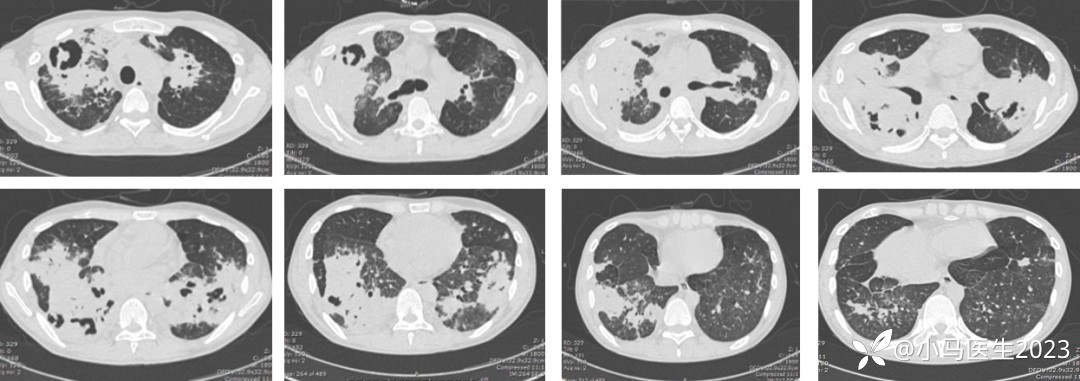

经皮肺穿刺

04-02

(右肺穿刺标本):送检组织镜下为坏死和少量残存肺泡,其中见反应性组织细胞,细胞浆内见球形病原体,特殊染色阳性,形态学倾向为荚膜组织胞浆菌,请结合临床

免疫组化结果:IgG(+),IgG4(-)。特殊染色:GMS(+),PAS(+),弹力纤维(显示肺泡壁破坏)

治疗

体温不降,氧合不佳,复查CT病灶进展

04-06 胸部CT仍进展

即刻追问病史及04-07病原体高通量检测